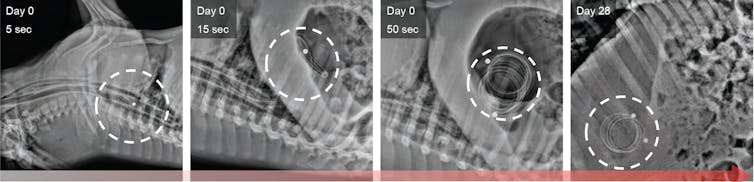

Inspired by the capacity of the stomach to hold large objects such as bariatric balloons, our group at MIT has recently designed a pills-on-a-coil system that can hold and release at least 10 grams of drug for one month. We have tested this in pigs. This system is able to dispense the quantity of antibiotics necessary to treat TB, the world’s leading killer among infectious diseases, for one month. Nonadherence to TB treatment, which requires at least six months of multiple daily pills, is a major reason the treatment fails.

Our pills-on-a-coil system consists of a coiled wire upon which medication is strung, like a candy necklace. The ends of the wire are protected in piece of tube with a magnet. The wire is superelastic and can be stretched to pass through the esophagus and then form a tight coil when it reaches the stomach. Cylindrical drug pills are made from mixing the drug with silicone followed by coating a thin layer of something called Eudragit RS 100. Silicone and Eudragit RS 100 are common materials used in long-term drug delivery to provide slow drug release. All pills simultaneously release a predictable amount of drug into the stomach. Once all drugs from the pills have been released, a separate retrieval device with a magnet can sense, attach and remove the coil from the stomach.